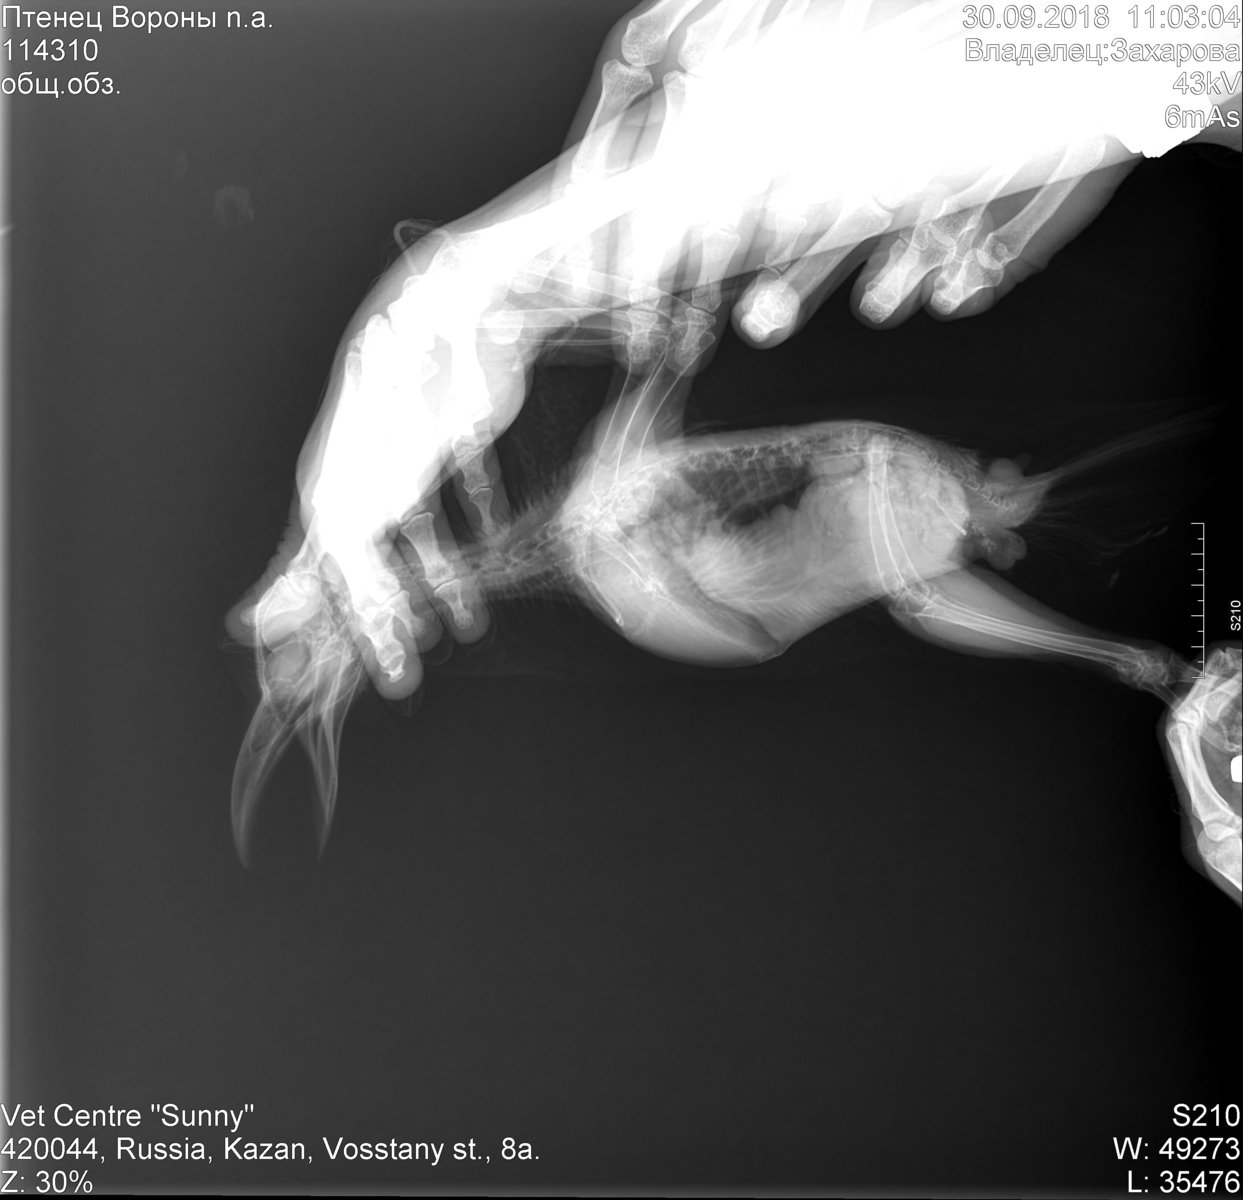

Dzakharova Опубликовано 1 октября, 2018 Автор #61 Опубликовано 1 октября, 2018 Добрый вечер! Не стала создавать отдельную тему, продолжу здесь. Вчера были у ветеринара, в связи с тем, что несколько недель был плохой стул. Сделали анализ на лейкоцитоз, взяди мазок из зева, посмотрели помет, сделали снимок. Как ьказалось, помет это можно сказать единственное что нормально, лейкоциты паравда тоже не повышены, мазок тоже без особенностей. Снимки прилагаю, также расшифровку ветеринара: По рентгену печень увеличена и рентгеноконтрастность повышена, воздухоносные мешки с затемнениями (птица не может летать, поэтому грибковое поражение очень может быть). Поэтому от глист обязательно птицу обработать, добавить в рацион насекомых, иммунофан, если можете, также продолжайте хотя бы месяц. Также я рекомендую на 2мес'продолжить кетаконазол по предыдущим назначениям, гептрал или гептор ( или же гепатовет) начинать давать. Вопрос, насколько все плохо? И мое традиционное - страдает ли птица? По состоянию он довольно крепкий, по крайней мере при всяческих манипуляциях очень бойко отбивается, аппетит хороший, активность у него стандартно не очень высокая.